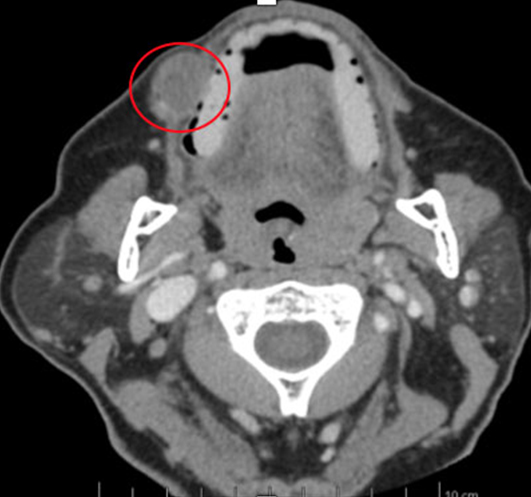

The team requested soft tissue ultrasound to determine clinical conduct. A nodule could be observed in the subcutaneous tissue of the right buccinator region, with well-defined and slightly lobulated limits, with apparent hyperechogenic bundle in its central portion, and with vascularization inside, measuring 2.1 × 1.3 × 1.4 cm. Subcutaneous cellular tissue was of normal echographic appearance and musculature was also of normal appearance and texture. The tomographic examination presented a hyperdense lesion in the region of the right buccal mucosa, between the buccinator muscle and the intraoral mucosa (Figure 2).

Figure 2: Computed tomography in axial section, showing a hyperdense image suggestive of nodular lesion in the lower right third of the face on the right side.